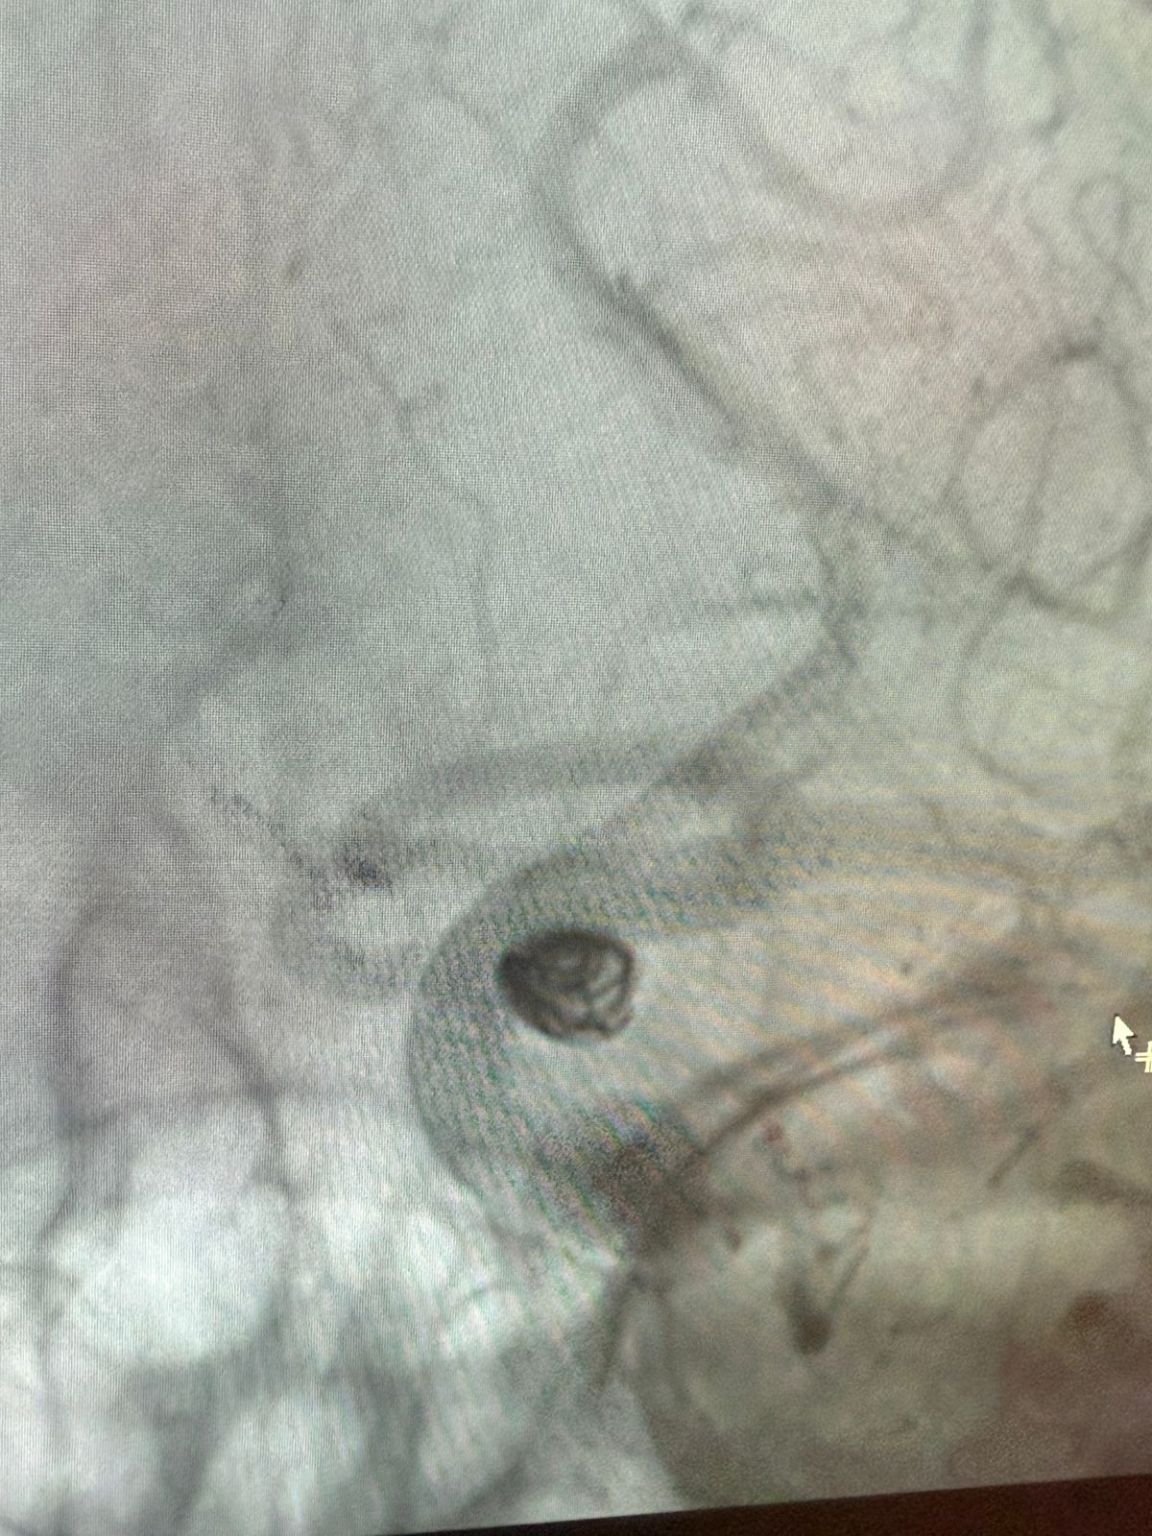

Le traitement a utilisé le Nuva®Déverseur d'écoulement (TJED-D 5.0-14), Perdenser®Bobine 3D, et Frepass®Microcathéter (TJMC18 Plus) pour un anévrisme de l'artère communicante postérieure.